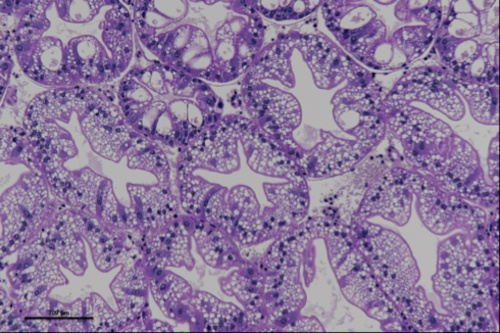

Katarina Bačnik, postdoc at National Institute of Biology (NIB), visited a lab at Istituto Zooprofilattico Sperimentale delle Venezie (IZSVe) in Legnaro, Padova, Italy from 10th to 15th August 2025, under the supervision of Dr. Tobia Pretto. The purpose of the visit was to provide education on sample preparation for histopathological analysis, processing of signal crayfish hepatopancreas samples, and designing a system for histopathological scoring of severity and frequency of observed histopathological changes, which was followed by examining samples under a microscope. Using high-throughput sequencing (HTS), we have previously characterized the virome of one of the most successful invasive freshwater invertebrate species in Europe—the crayfish (Pacifastacus leniusculus)—and identified novel and divergent RNA viruses associated with this species along its invasion range. Some of the viruses present in the invasive host can cause histopathological changes in tissues, as previously observed in the high incidence of idiopathic necrotizing hepatopancreatitis (Bekavac et al., 2022).

Using the newly obtained knowledge, we aim to implement the histopathological analysis of invertebrate samples in our lab at National Institute of Biology (NIB), in the case of hepatopancreas samples using the designed binominal scoring to describe the overall presence/absence of histological changes and ordinal method with scoring of several test fields.